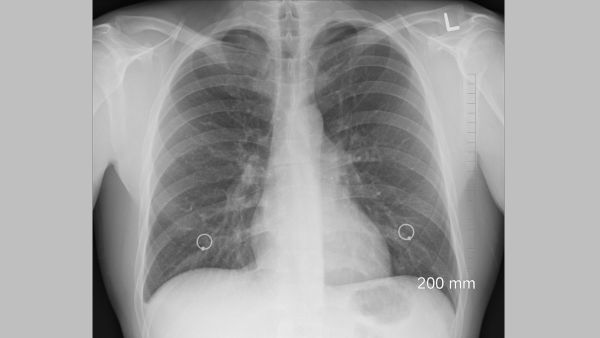

In a chilling global scenario reminiscent of recent pandemic woes, a new health concern is making waves - White Lung Syndrome. This mysterious pneumonia, affecting children aged three to eight in China, Denmark, the United States, and the Netherlands, has raised alarms globally.

What Is White Lung Syndrome?

White Lung Syndrome isn't just like any other pneumonia; it's a serious threat that can lead to lung scarring and discoloration. The impact is severe, making global health organizations closely watch and study how the disease develops. The exact details of this illness highlight the urgent need for researchers to work together and understand its complexities.

The seriousness and distinct features of lung damage observed on scans make understanding this health issue even more puzzling.